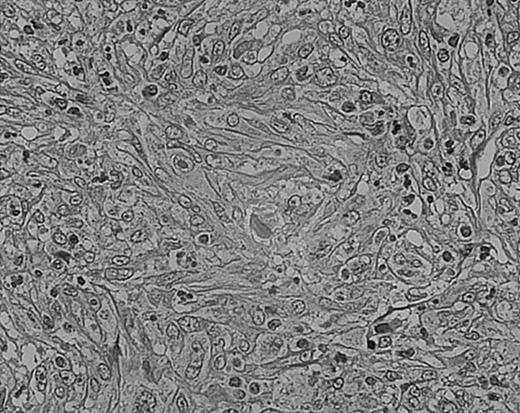

As we have previously reported, tissue eosinophilia is the strongest prognostic indicator in NS.19 Eosinophilia was not included in the BNLI criteria. We therefore propose a new grading system that includes this important risk factor and should be easier to use than the BNLI criteria. The 3 criteria of the new grading system are: eosinophilia (approximately > 5% of all cells or clusters in at least 5 high-power fields; new feature; Figure5); lymphocyte depletion (< 33% of all cells in the whole section; simplified feature of BNLI; Figure6); and atypia (> 25% of H/RS cells bizarre and highly anaplastic appearing, with pleomorphic nuclear features, hyperchromatism, and highly irregular nuclear outlines; simplified feature of BNLI; Figure 7). Cases showing none of these factors are called NS-low risk (NS-LR) and each case showing one or more of the factors is called NS-high risk (NS-HR).

Lymphocyte depletion in NS HD.

This example shows lymphocytes in less than 33% of all cells. Stained with H&E. Original magnification, × 400.